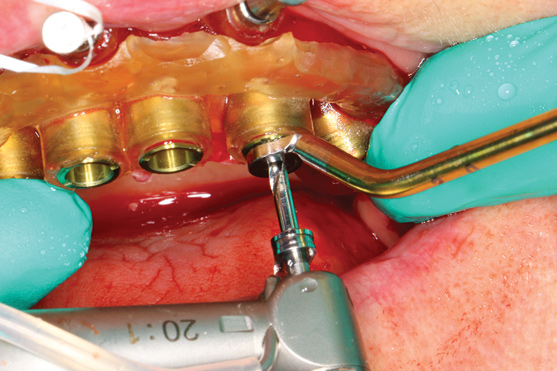

The workflow described in this case is just one example, and there are numerous ways to achieve the same goal. This particular workflow is relatively easy to execute and efficient from the standpoint of planning, fabrication, and clinical application. Figure 11 and Figure 12 demonstrate the accurate placement of the implants as can be seen by the copings exiting directly into the openings in the printed provisional. The provisional was indexed and the copings picked-up by injecting a provisional bisacryl composite resin. The finished 3D-printed provisional was characterized with pink composite and fixated to the implants with abutment screws, and the access holes were sealed with sterilized teflon tape and composite resin (Figure 13).

Fig 12. Provisional seated over implant copings.

Figure 12